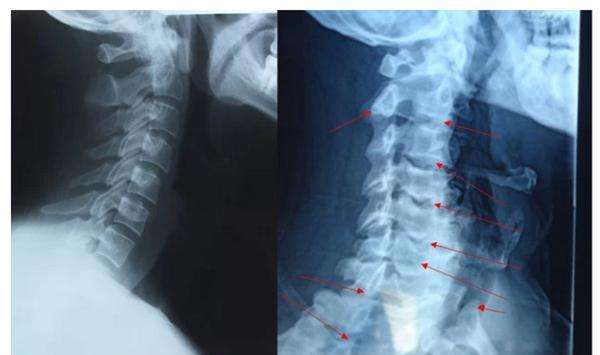

2、骨刺,只是X光片上看起来很尖,实际上并不是

是的,虽然X光片上看骨刺都是尖尖的,好像尖刀一样,但实际上,骨刺并不是尖的,而是钝的。

骨科医生在做手术时都会知道,那些在X光片上看起来尖尖的骨刺,在切开后会看到,其实骨刺表面包着一层圆润钝钝的软骨或结缔组织。只是这层圆润钝钝的软骨和结缔组织在X光片上不显示,只显示下面的骨头,所以尽管在片子上看骨刺好像是尖尖的,但是其表面其实是包着一层圆润的软骨的,并不会扎伤什么。